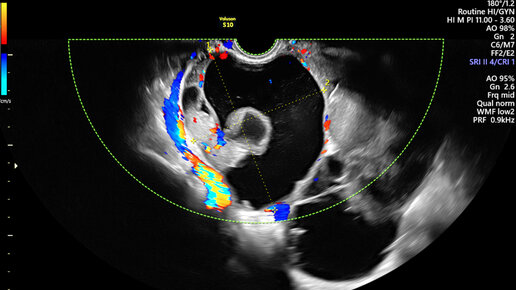

Почему важно наблюдаться у гинеколога? Нужно ли посещать врача, если ничего не беспокоит? Болит ли рак и как он проявляется на ранних стадиях? Какие гинекологические проблемы характерны для периода менопаузы,...